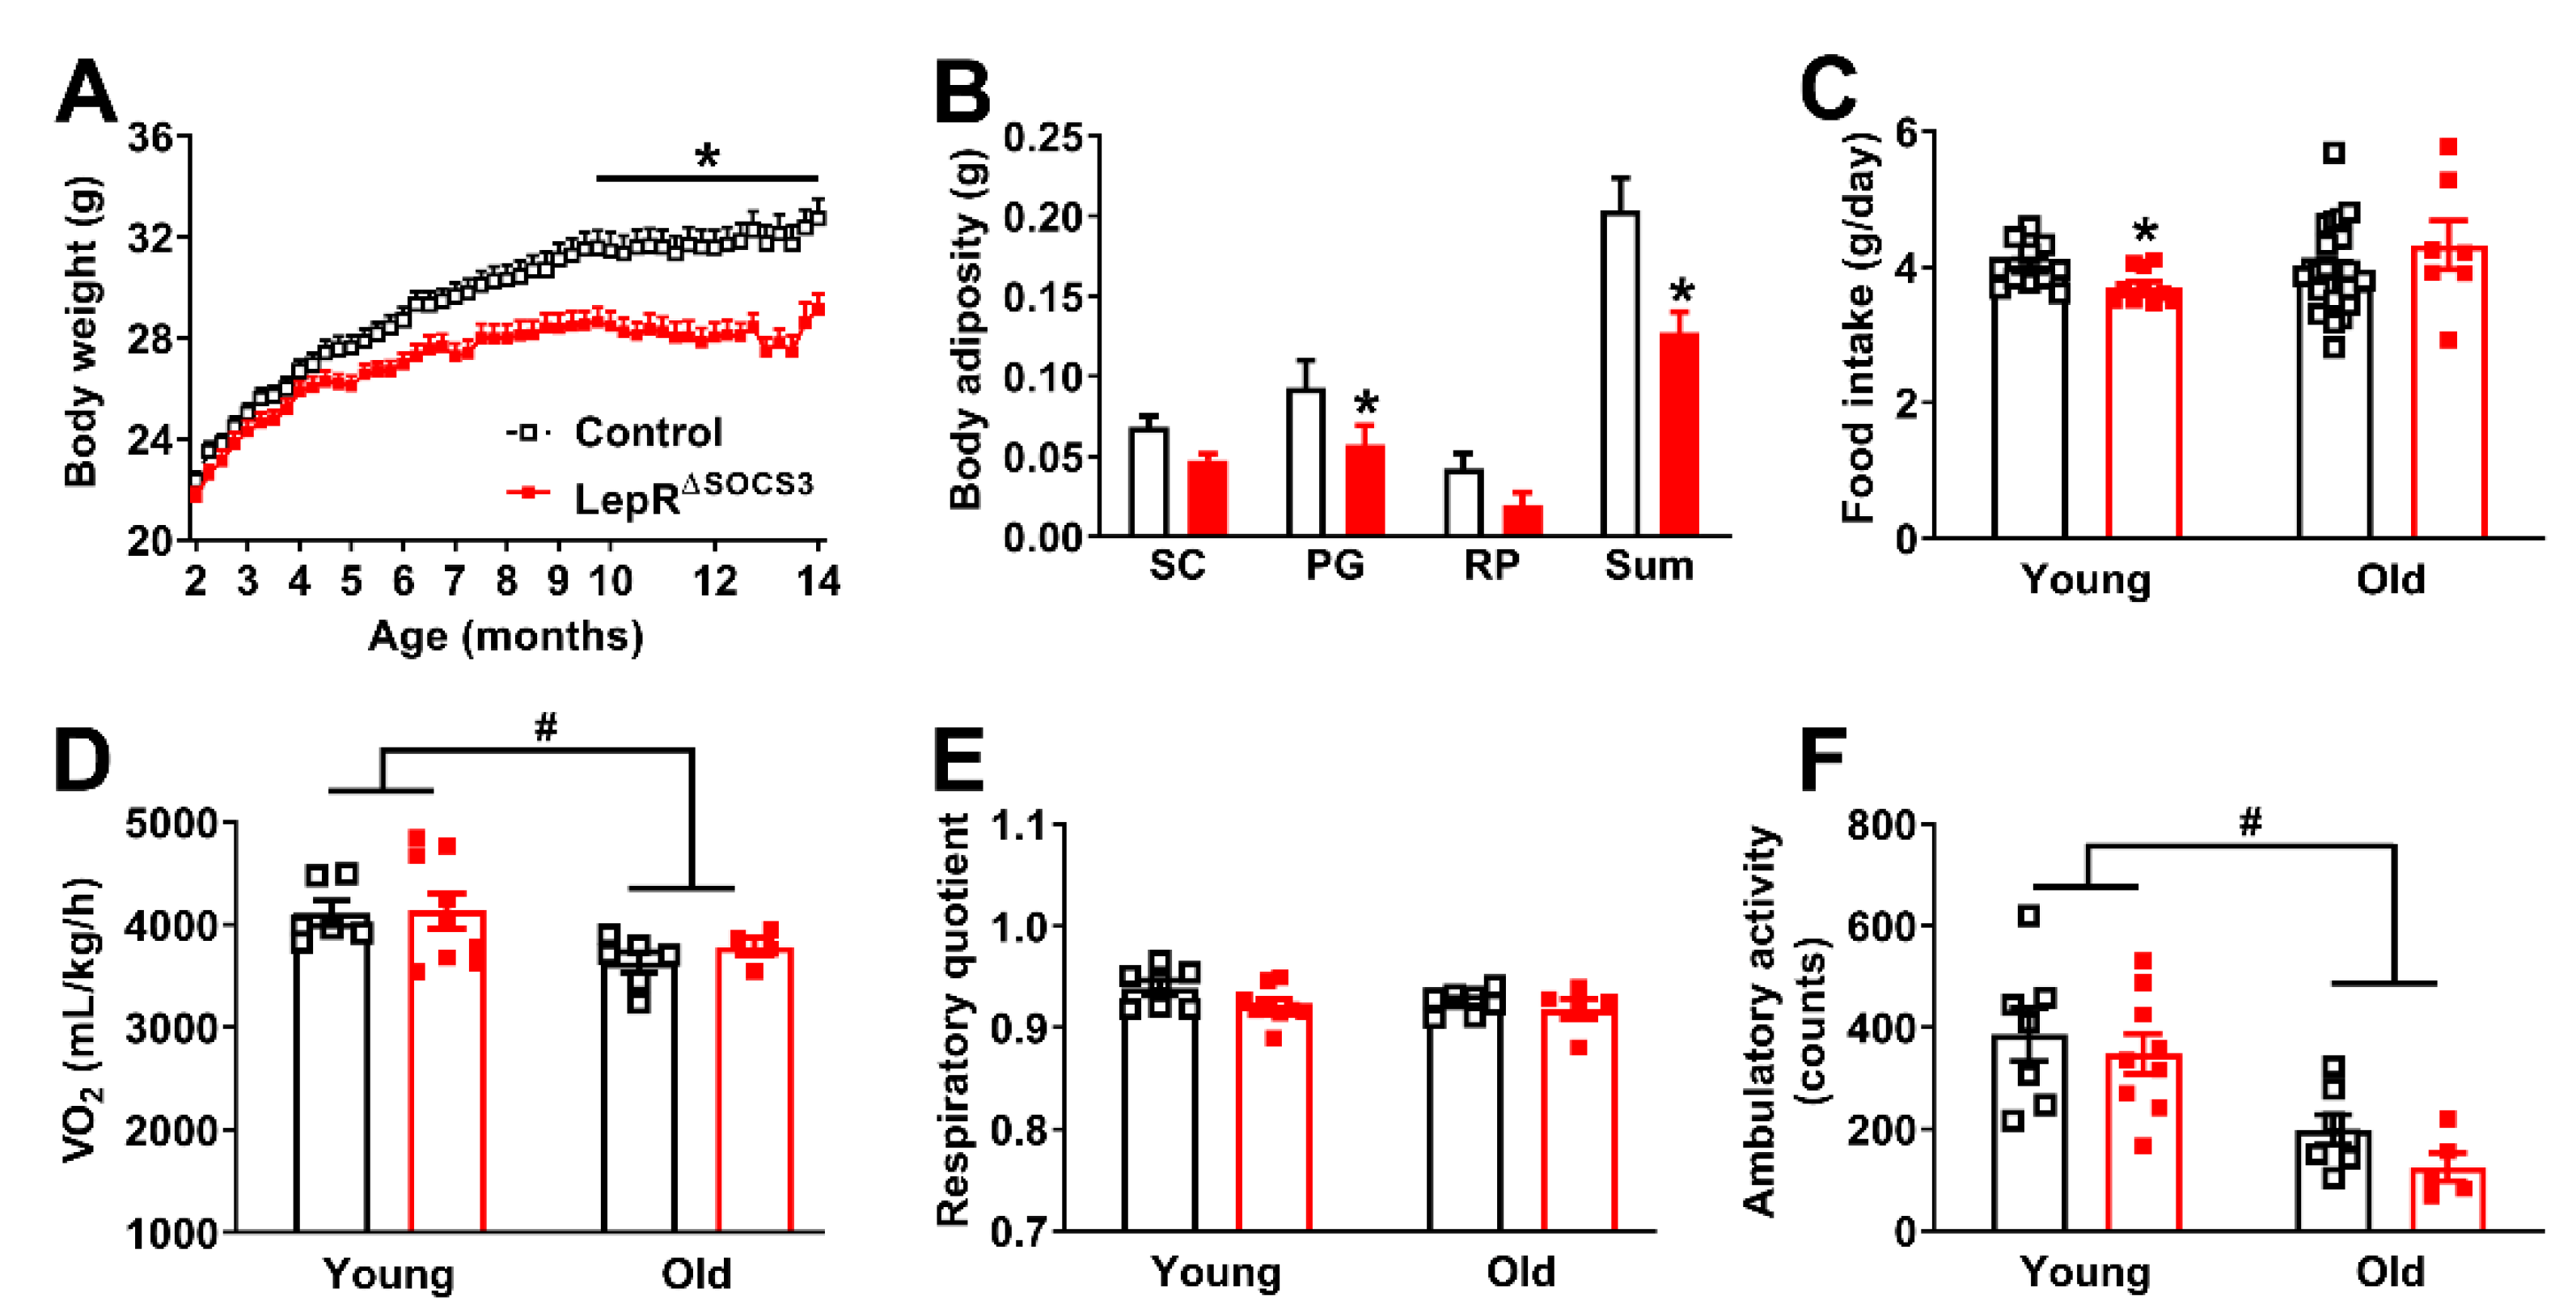

2.1. SOCS3 Ablation in LepR-Expressing Cells Improves Energy and Glucose Homeostasis in Aging Mice